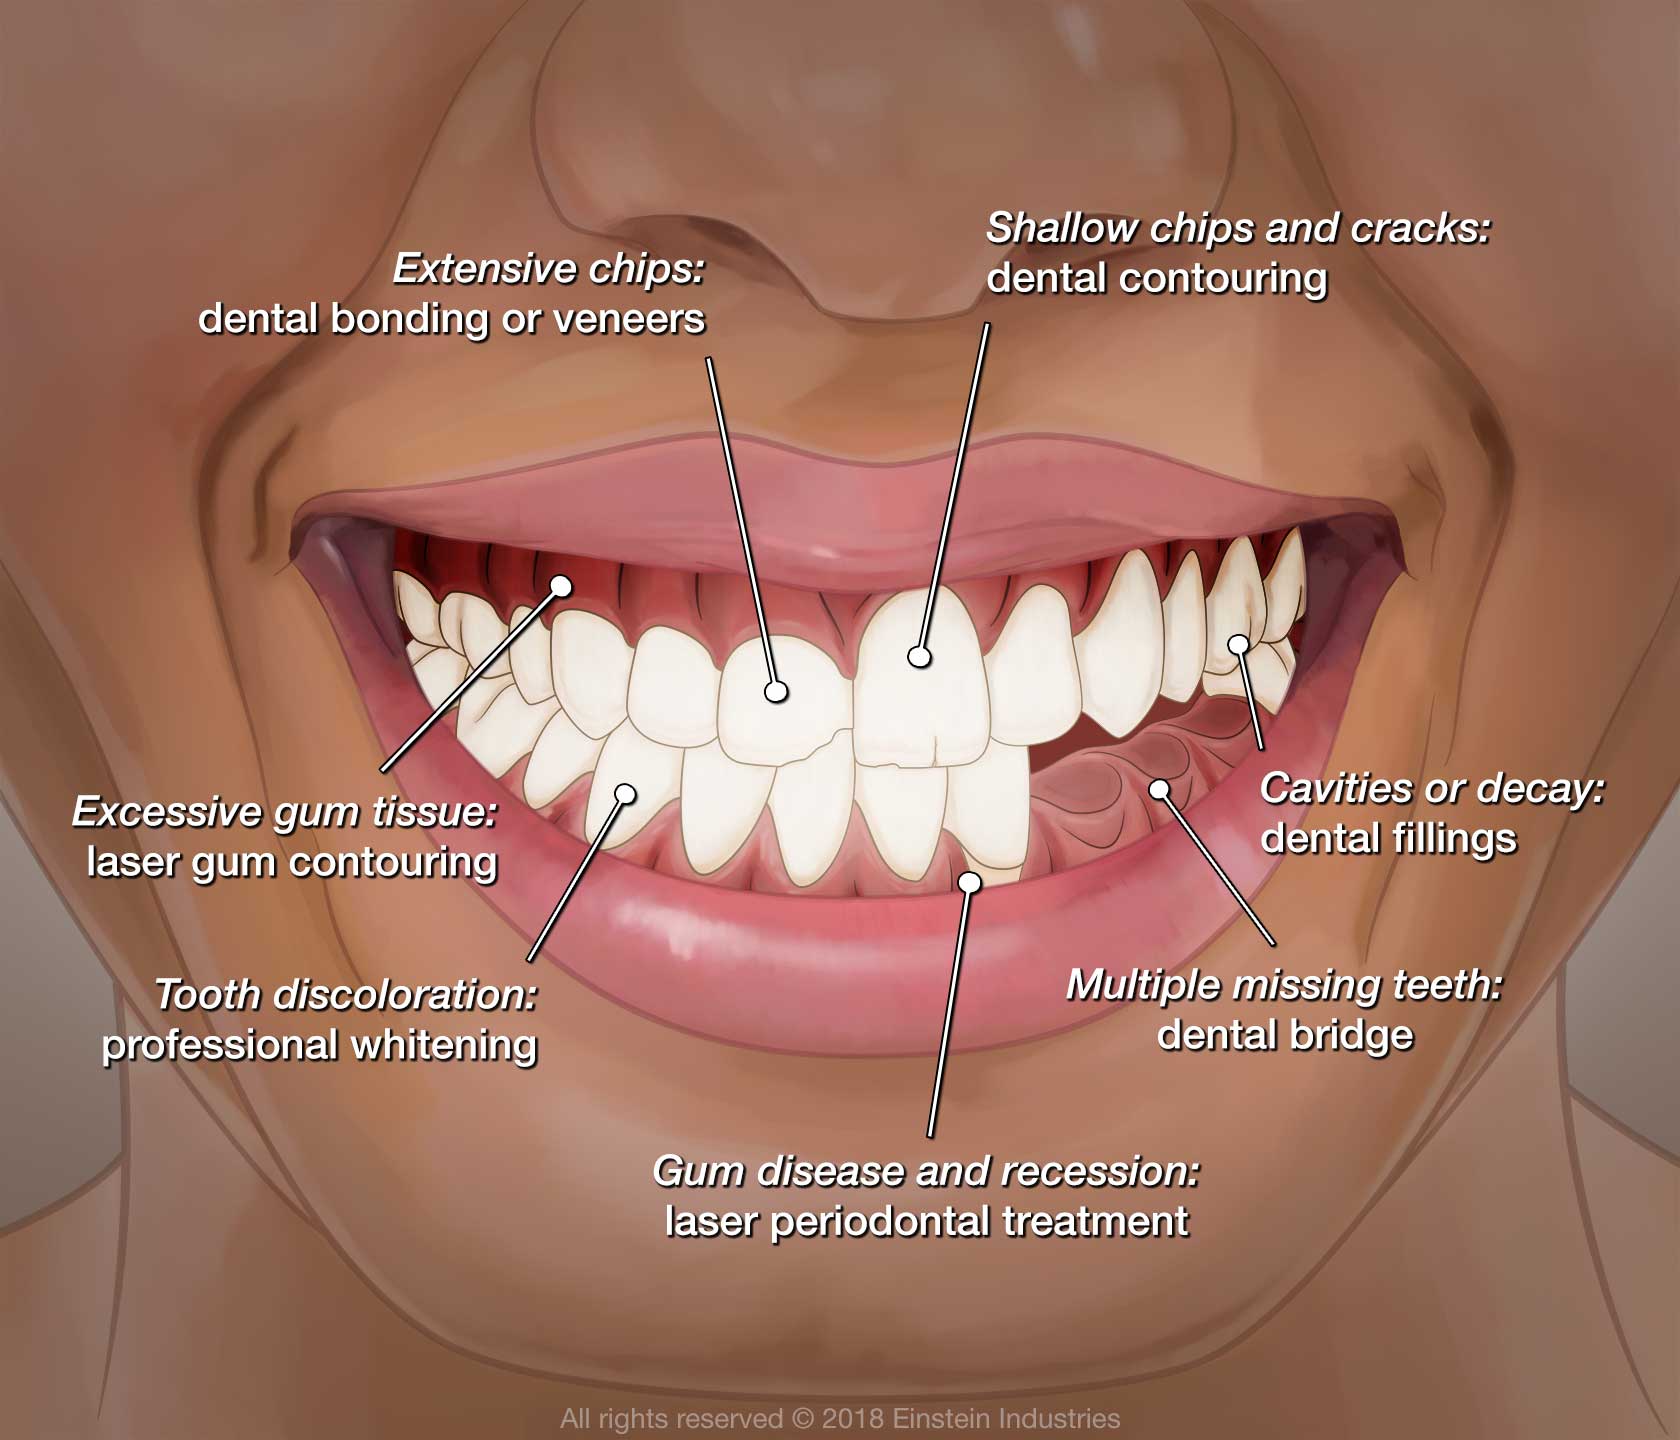

Common Cosmetic Dentistry Procedures

Dental Bonding

This minimally invasive procedure involves the application of composite resin to the affected areas. Bonding can conceal minor imperfections like chips, cracks, and tooth discoloration. Once complete, the results last about five to seven years on average. Because it does not require the removal of enamel, this procedure is reversible.

Porcelain Veneers

Teeth Whitening

Smile Makeover

If you have multiple cosmetic issues, a smile makeover is an excellent solution. This treatment plan combines two or more procedures. For instance, many individuals combine porcelain veneers and teeth whitening for more comprehensive results. Each smile makeover plan is custom-designed to meet your unique needs.

Combining Cosmetic and Restorative Dentistry